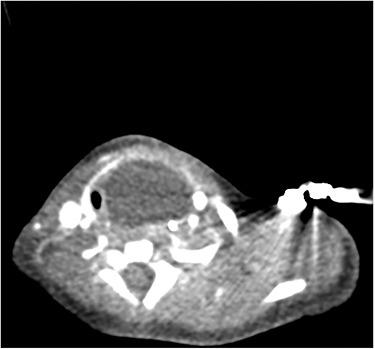

Congenital oesophageal diverticulum is incredibly rare and has not commonly been published in the literature. Oesophageal diverticulum can be asymptomatic; however, symptoms such as dysphagia, regurgitation and chest discomfort may be present. We describe the case of a paediatric patient presenting with biphasic stridor, respiratory distress and cyanosis at birth, who was found to have a supraglottic cyst and later the presence of an oesophageal diverticulum shown on ultrasound imaging. There has been one other case reported in the literature of an oesophageal diverticulum presenting with stridor, and we therefore believe this is one of only two cases to illustrate this atypical presentation of congenital oesophageal diverticulum. It highlights the importance of a meticulous multidisciplinary team approach to patient care, as well as conducting appropriate investigations to aid early diagnosis to improve patient outcomes.